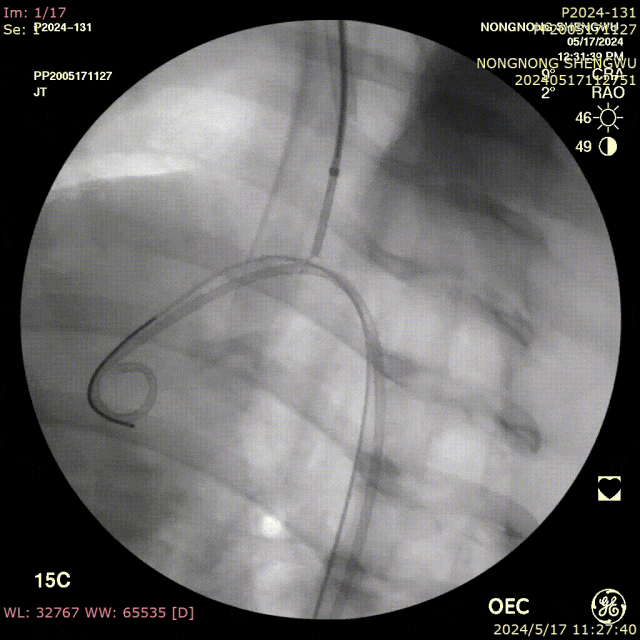

我们在两头35kg巴马公猪中完成动物实验:

成功实现弓上分支的快速、准确原位开窗;

破膜过程流畅,无分支或主动脉损伤;

取出标本可见圆形破口、支架贴合良好,证实技术可行性。

动物实验

巴马公猪35kg